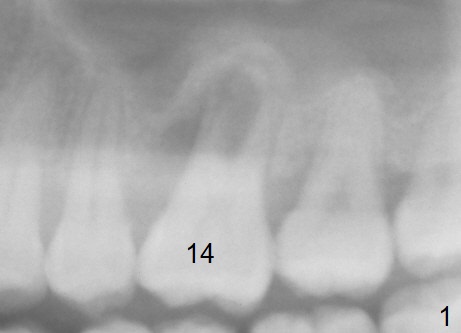

A 41-year-old man has had severe periodontitis at #14 for the last 11 years (Fig.1-3). Finally the tooth is mobile. Draw blood for PRF membrane (x4). After use of Magic Drill with 3 mm stopper, tap Magic Lifter for sinus lift. Insert 1-2 PRF membrane(s) and Vanilla graft prior to further osteotomy with UF drills until 4.5 or 5 mm. Insert tap drill for primary stability. If it fails, switch to IBS dummy implants.

4